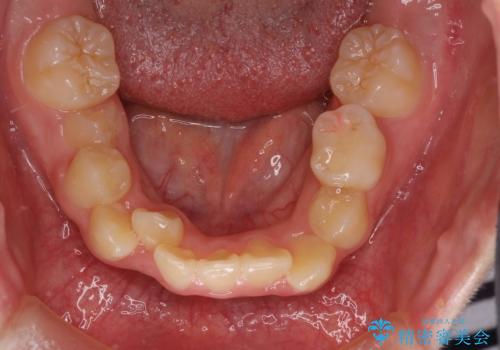

- 乳歯の晩期残存による永久歯の萌出遅延・過剰歯・萌出異常

など多くの問題を抱えていた。

乳歯がうまく抜けず、過剰歯が存在していたことにより、永久歯が位置異常をおこし、非常に複雑な状況となってしまっていました。